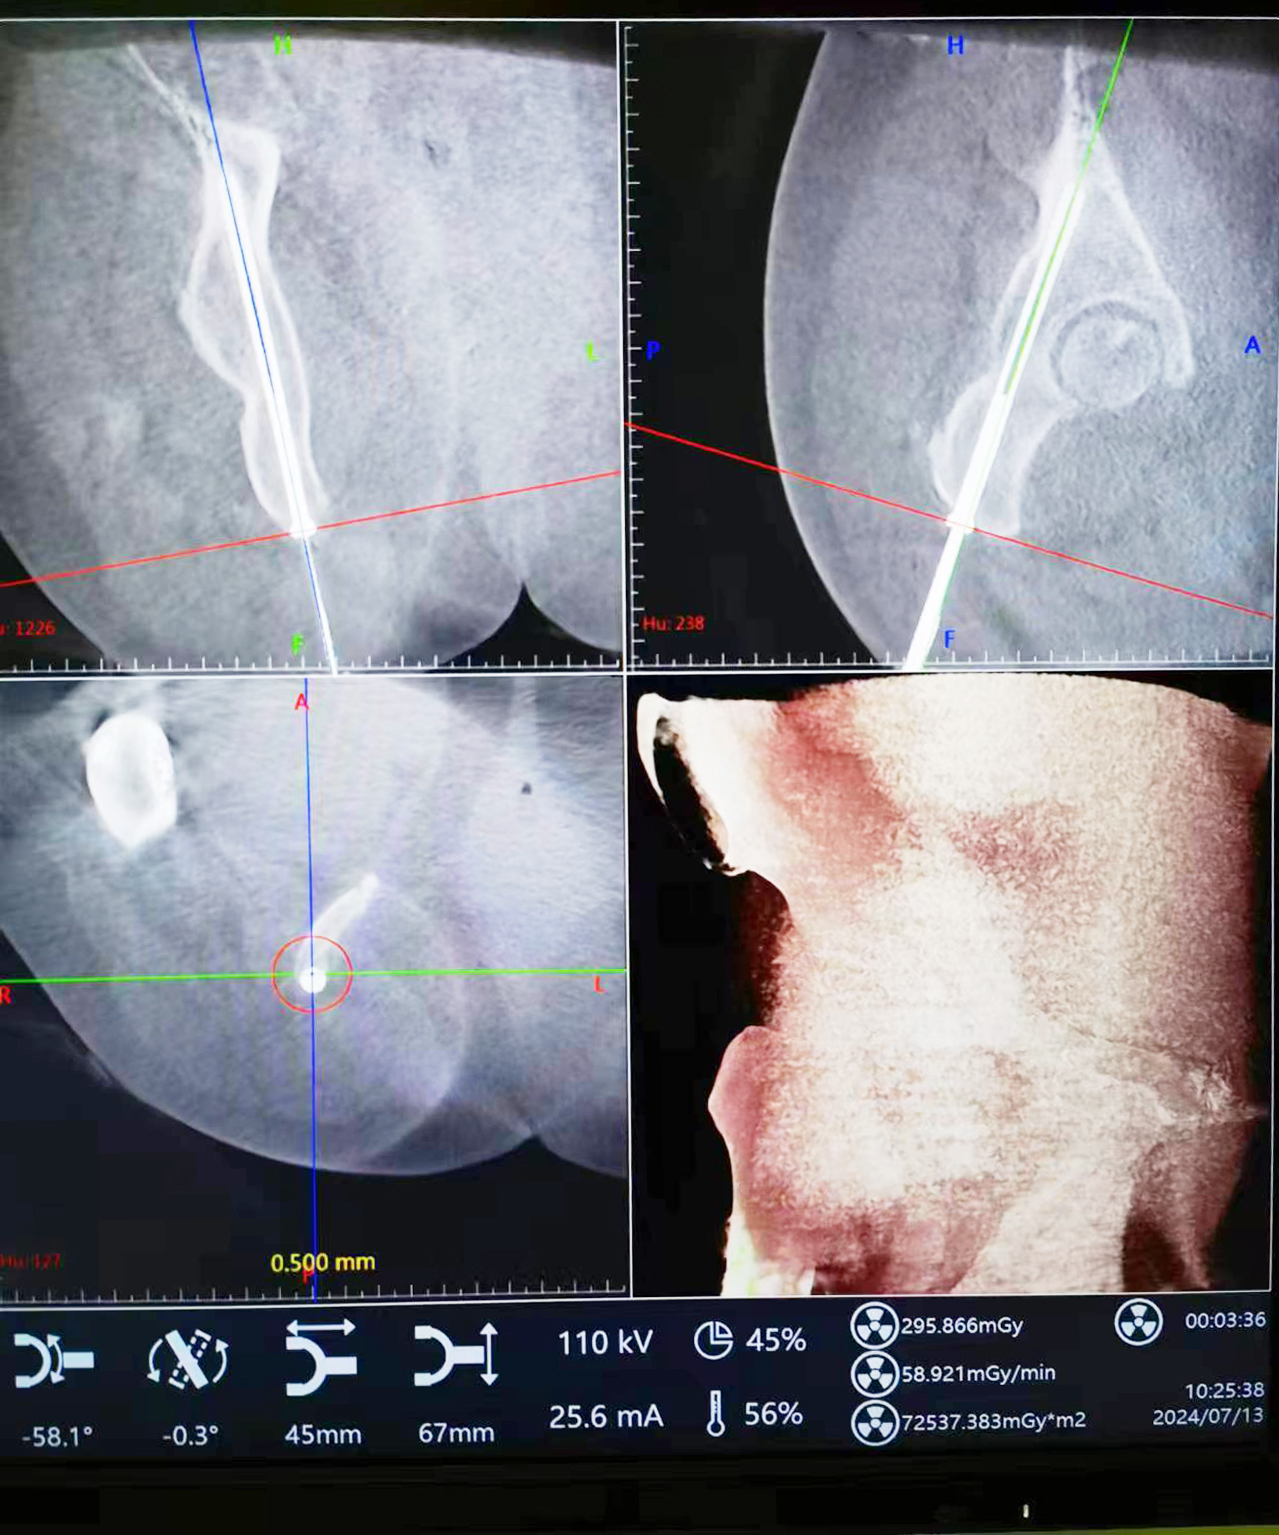

患者,女,50歲,因“車禍傷致右髖部疼痛伴活動受限2h”收住院,診斷為“右側髖臼后柱骨折”。入院后,劉志主任及宋遠征主治醫師綜合評估患者病情及骨折類型后,決定給予患者行“機器人導航輔助下微創經皮后柱通道螺釘內固定術”。

術中將示蹤器用克氏針固定于患側髂后上棘,將采集到的圖像傳輸至主控臺用于對骨盆通道螺釘進行路徑規劃,選擇螺釘直徑、長度、入點、止點。在遙控導航下,機器人將機械臂沿著規劃路徑移動到目標位置,置入導針和螺釘。術中驗證髖臼后柱螺釘置入位置精準,切口1.0cm。